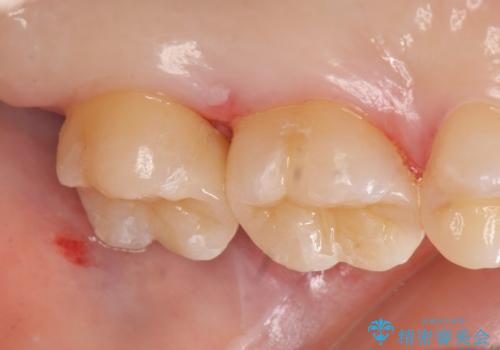

術後歯肉の回復を待ち、左下6、7ともにセラミックインレーによる修復を行いました。

セラミックインレーについて

当院のセラミックインレーはemaxという強度と審美性に優れた材料を使用しています。

またプレス方式でインレーを製作しているため、削り出しで製作するCADCAMより優れた適合性も持ち合わせており、虫歯が再発しにくい修復物です。